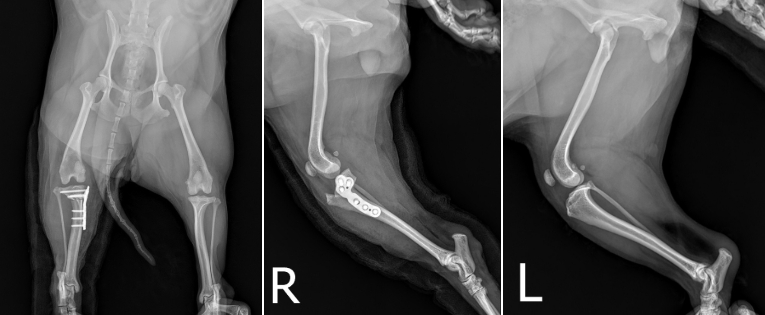

수술 후 엑스레이를 재촬영 하여 잘 진행되었는지 평가합니다.

환자는 무릎 각도가 수술 후 얻고자 하는 각도로 잘 변형 된 것으로 보였으며 플레이트와 스크류도 뼈 내 잘 안착 된 것으로 확인되었습니다. ▼